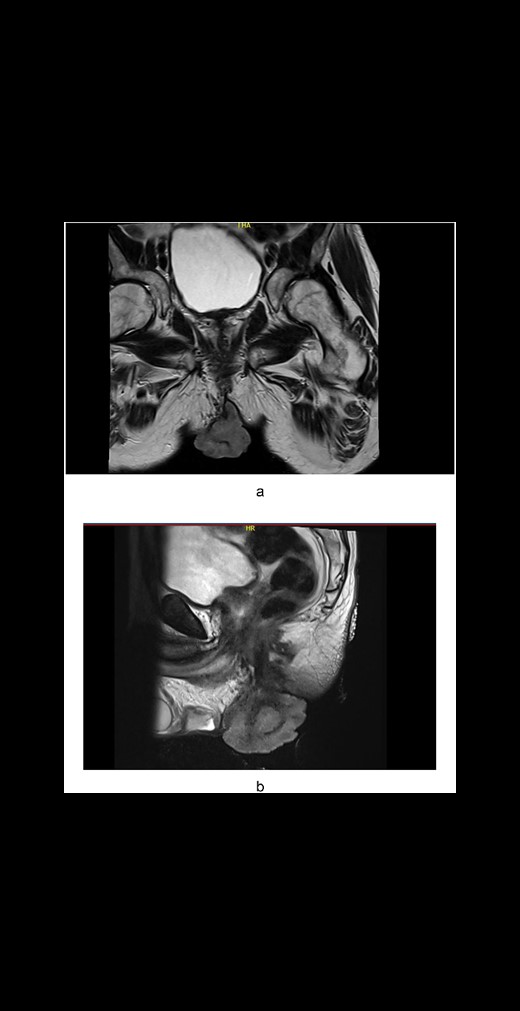

A male in his late 50s was referred to our surgical unit with a significant perianal mass, described as 10 cm × 15 cm, fungating, purulent, and malodorous, accompanied by fresh per rectum bleeding. Noted initially 12 months before presentation, the mass exhibited progressive enlargement. The patient's history of extensive smoking compounded the clinical concern. The patient reported no history of involvement in men who have sex with men behaviours. Diagnostic imaging, including CT of the abdomen and pelvis, showed no evidence of metastatic disease, and comprehensive virological screening was negative. Magnetic resonance imaging (MRI) of the rectum and pelvis (Fig. 1a and b) delineated a large perianal mass with characteristics suggestive of giant condylomata acuminata of Bushke–Löwenstein (Fig. 2), prompting further diagnostic refinement through examination under anaesthesia and targeted biopsies, which corroborated the suspicion.

(a) Axial plane MRI pelvis: A large perianal mass. (b) Sagittal plane MRI pelvis: A large perianal mass